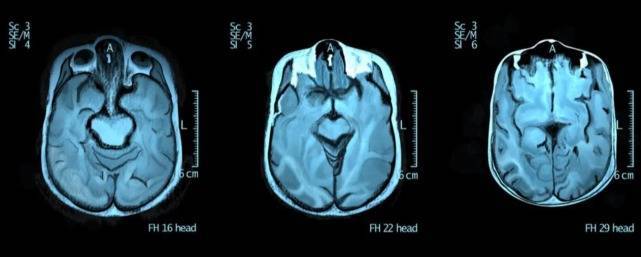

根据《自然》杂志上的一篇报告,自闭症患者大脑的左右脑比普通人的更加对称,而左右不对称的大脑才能够更加协调“互动”。

图注:自闭症患者的大脑更加对称

我们的思维和认知过程在左右脑之间来回穿梭,而闭症患者大脑左右两边的交流有点困难,或者两边没有那么多紧密联系。

另外,自闭症患者大脑的灰质和普通人也不太一样,大脑的灰质越多,则意味着可以处理的信息就越多,而有些自闭症患者会在某些区域灰质突然显著增多,这可能是他们变成某方面“天才”的原因。